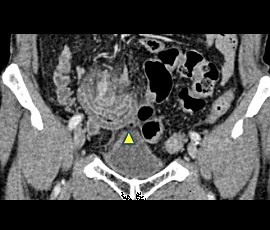

急性腹症にて救急受診。CT検査にて、下腹部正中右側の回腸遠位部に腸管壁肥厚と周囲の脂肪織濃度上昇および微小な遊離ガス像を認め、内部に嚢胞性病変を認めた。精査の結果、メッケル憩室炎、穿孔と診断。緊急手術(腹腔鏡下小腸切除術手術(単孔式))を施行した。

CT画像